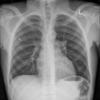

normal vessels

Date: 01/12/2015

Views: 3365